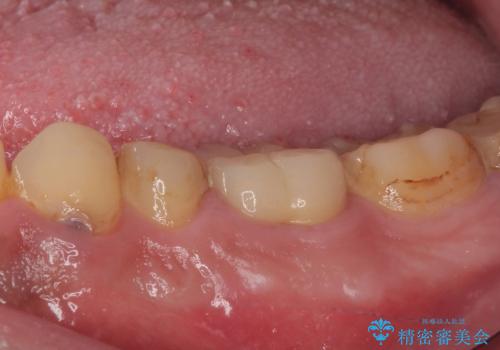

病変が消退しているかどうか、半年、1年とレントゲン写真で経過観察を行う必要があります。

4ヶ月後のレントゲンでは、病変の消退が認められました。